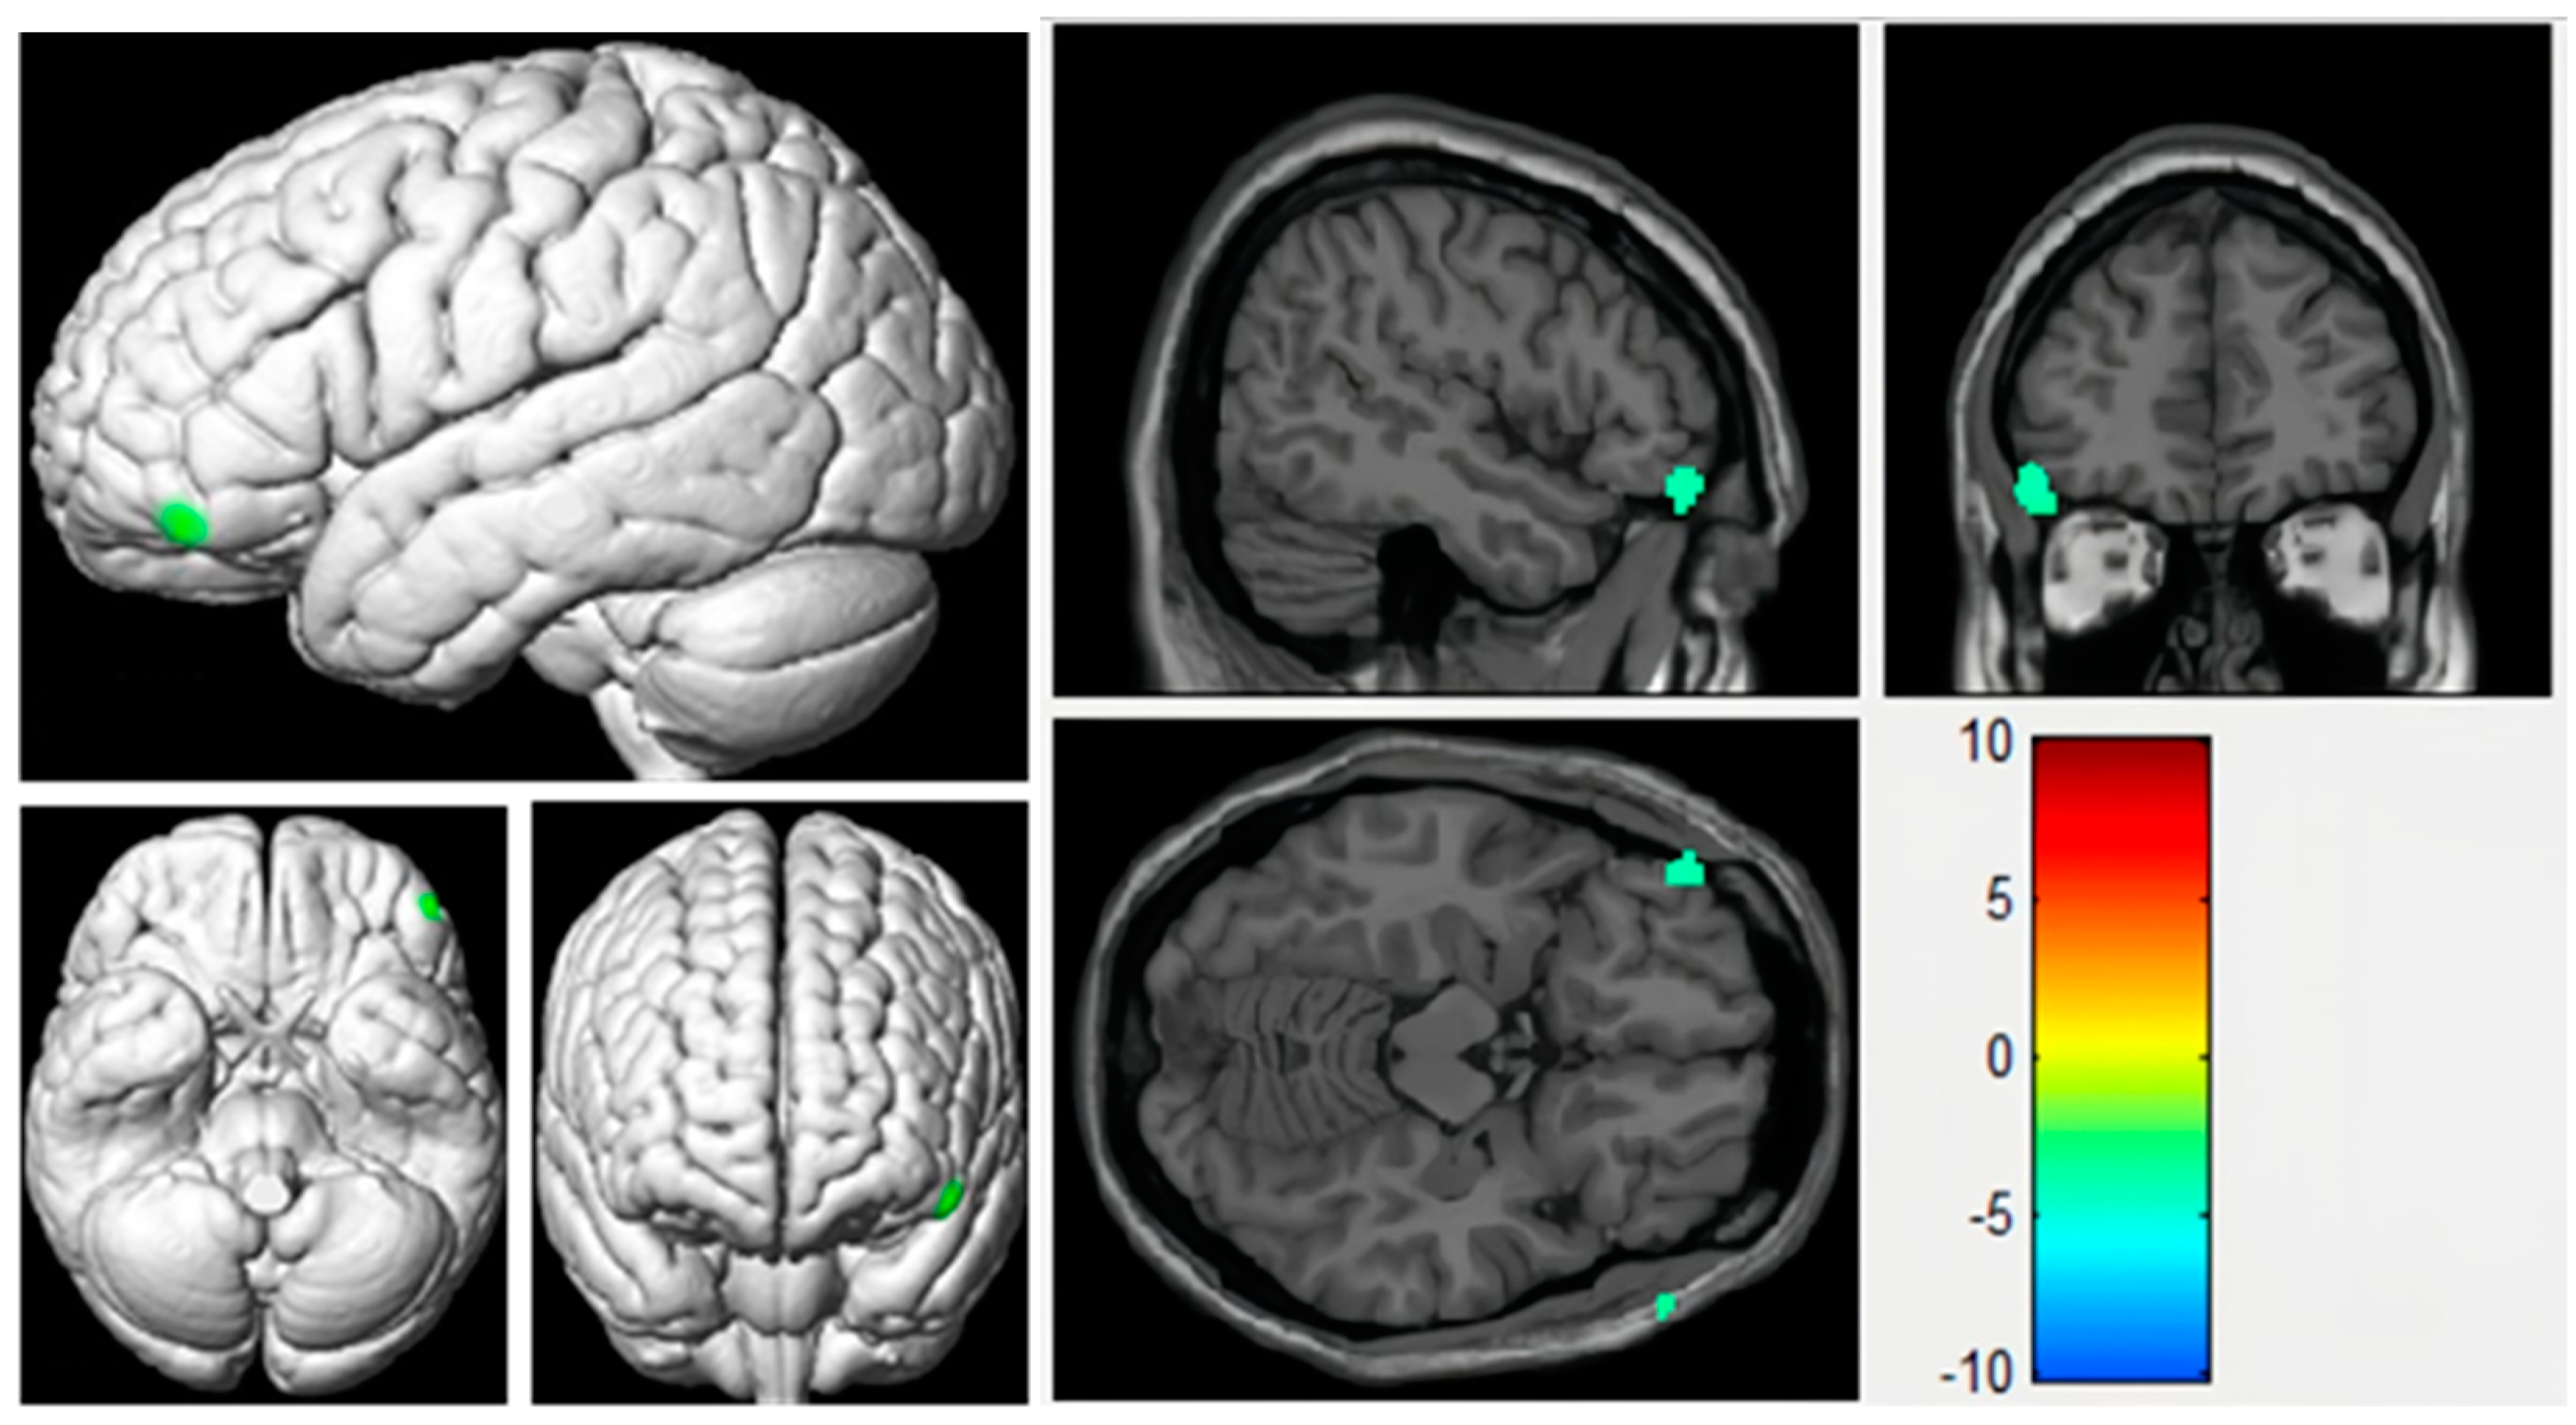

3.2. Voxel-Based Analyses of CBF Maps Based on ASL

| Brain Area | Peak MNI Coordinate | Cluster Size | Statistical Value (T) | ||

|---|---|---|---|---|---|

| x | y | z | |||

| Left inferior frontal gyrus | −52 | 46 | 16 | 14 | −4.3251 |